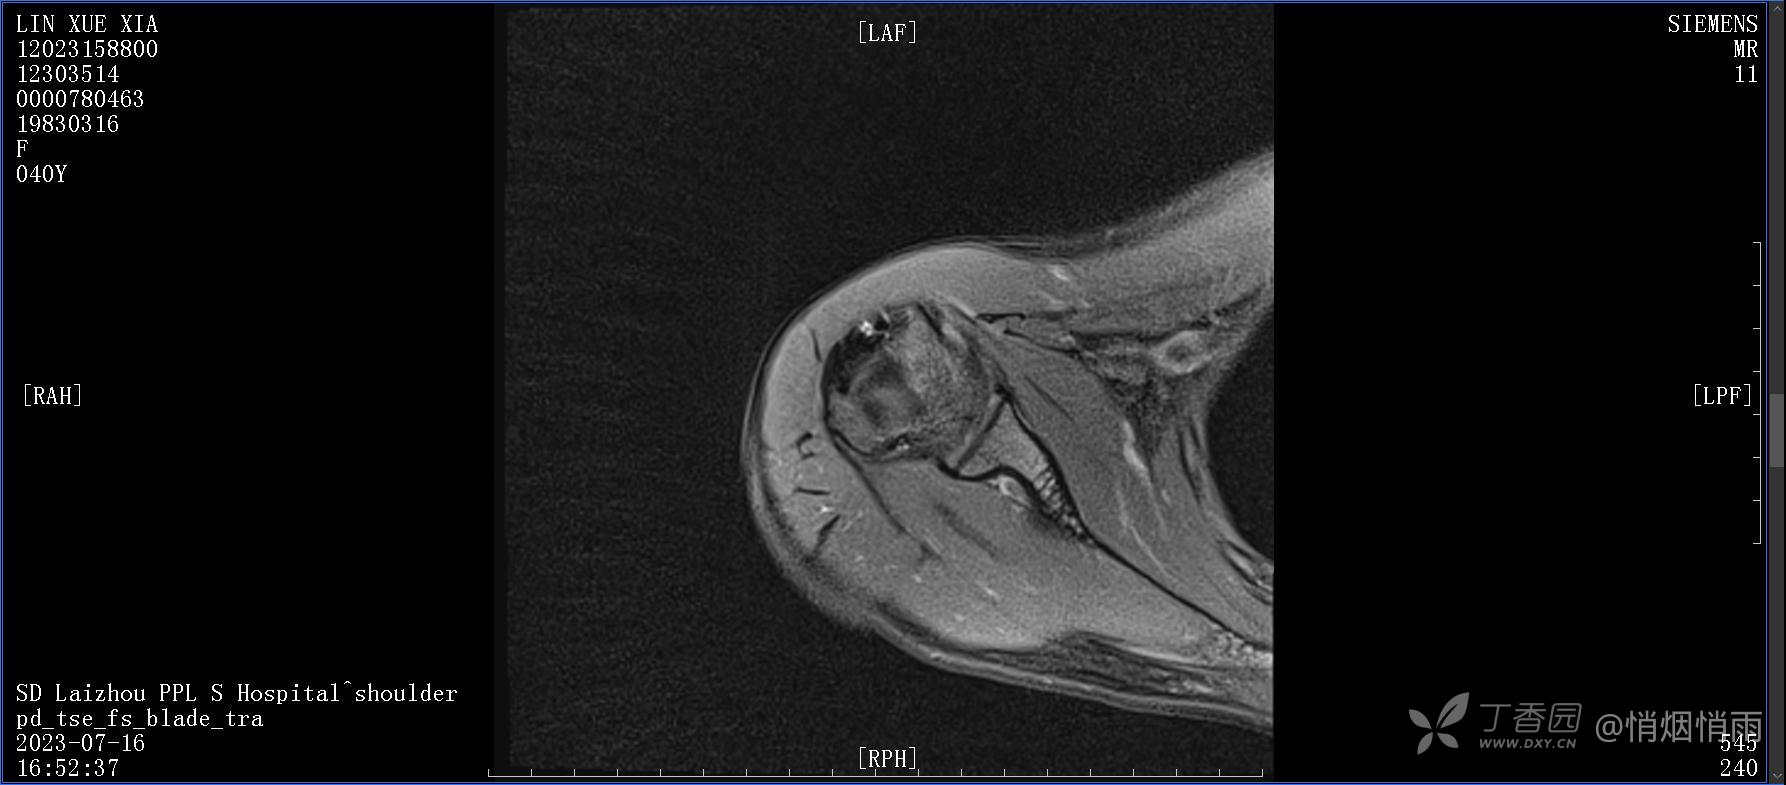

查体:右肩关节局部轻度肿胀,肩胛区压痛明显,痛处不固定,肩关节痛性活动受限,jobe test(+),lift -off test(+),中指、环指感觉较余指减退,余肢端感觉及血运情况可。

目前的诊断,暂时依据辅助检查诊为肩袖损伤,但是患者疼痛的性质和特点,却不是单纯的肩袖损伤所致。考虑过胸廓出口综合征,但是该疾病会出现肩胛区的疼痛吗?(由于考虑到费用的问题,没再进行下一步的检查)带状疱疹会有如此的症状吗?